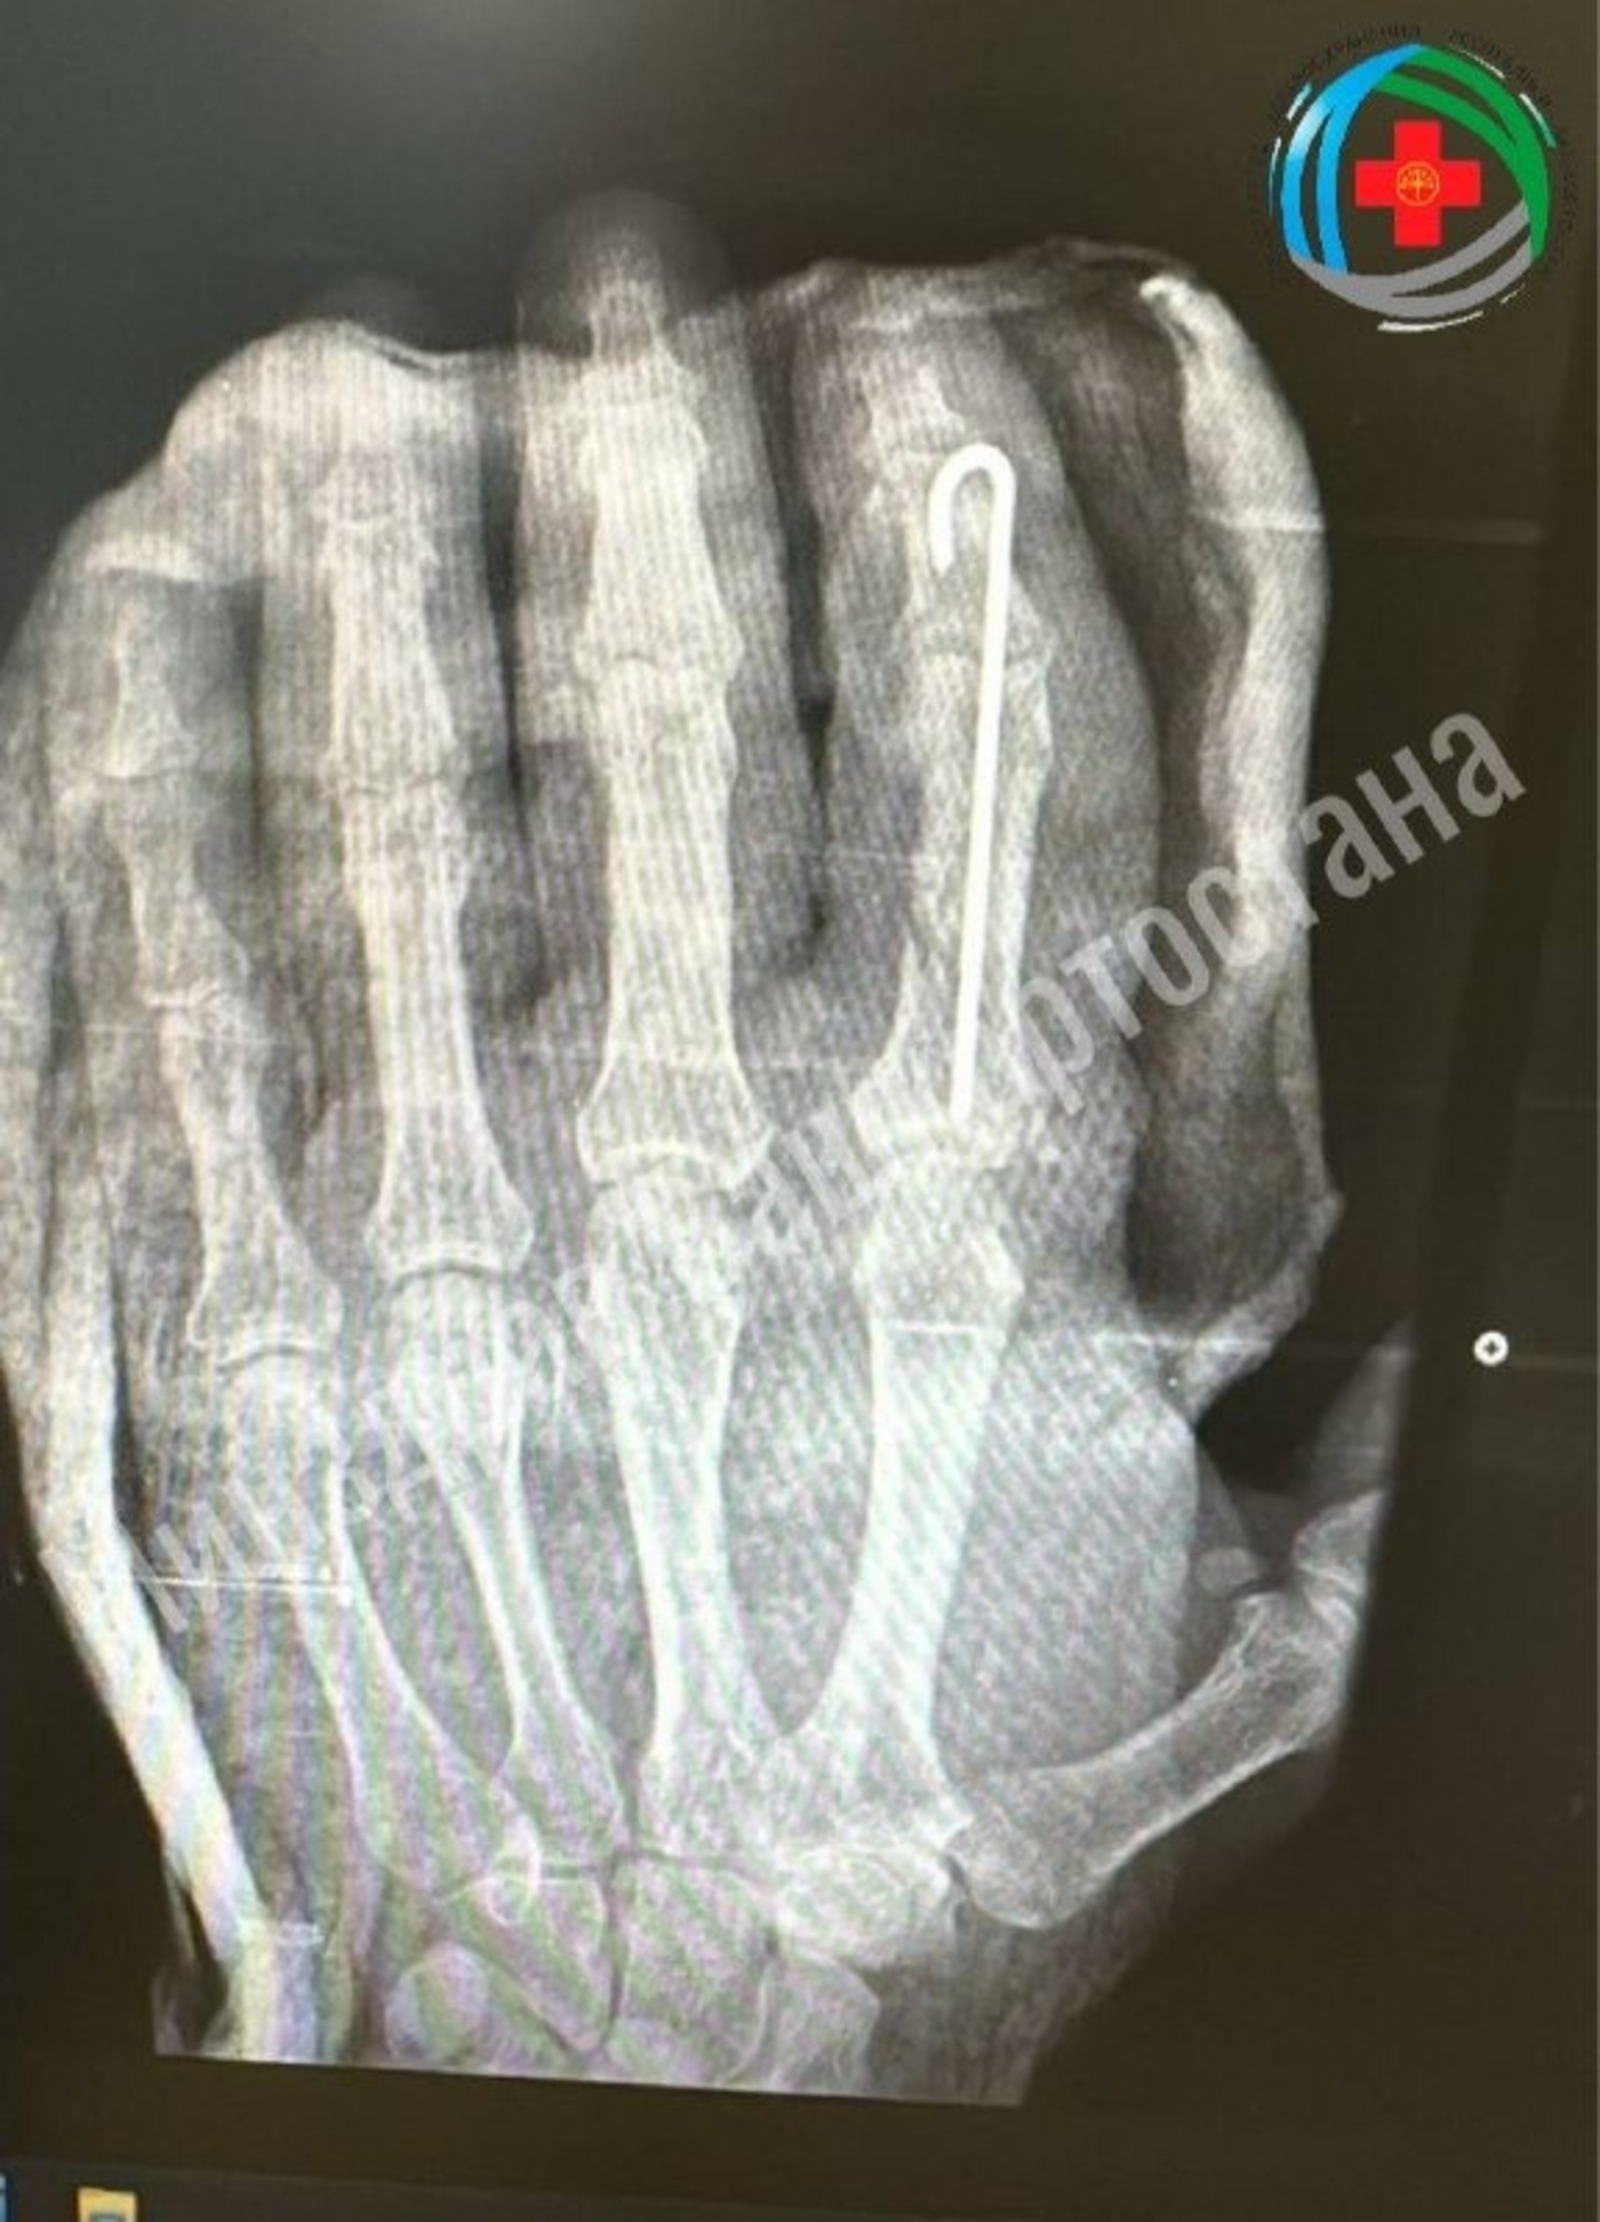

Пуртăпа касса татнă пÿрнине çĕлесе сыпăнтарнă

Вырăнти тухтăрсем Благовещенск районĕнче пурăнакан çыннăн касса татнă пÿрнине çĕлесе сыпăнтарнă.

ПР Сывлăх сыхлав министерствинче пĕлтернĕ тăрăх, арçын ăнсăртран пÿрнине пуртăпа касса татнă пулнă. Тĕрĕсленĕ хыççăн хирургсем васкавлă операци ирттересси пирки йышăну тунă.

Вĕсем чăн-чăн ювелир ĕçĕ пурнăçланă. Юн çÿреме пуçлатăр тесе чи пĕчĕк юн тымаррисене сыпăнтарнă, шăммисене тĕрĕс çирĕплетнĕ тата пÿрни туллин ĕçлетĕр тесе ÿтне çĕнетнĕ.

Пÿрне лайăх ÿт илнĕ. Арçын пÿрнине кăштах хускатма та пултарать. Халĕ вăл сиплев медицини иртет, ун шутне эмелпе сиплемелли терапи, физиотерапи тата сывату физкультури кĕреççĕ. Сывату результачĕсем тăрăх, пÿрни пĕтĕмпех юсанасса шанаççĕ.